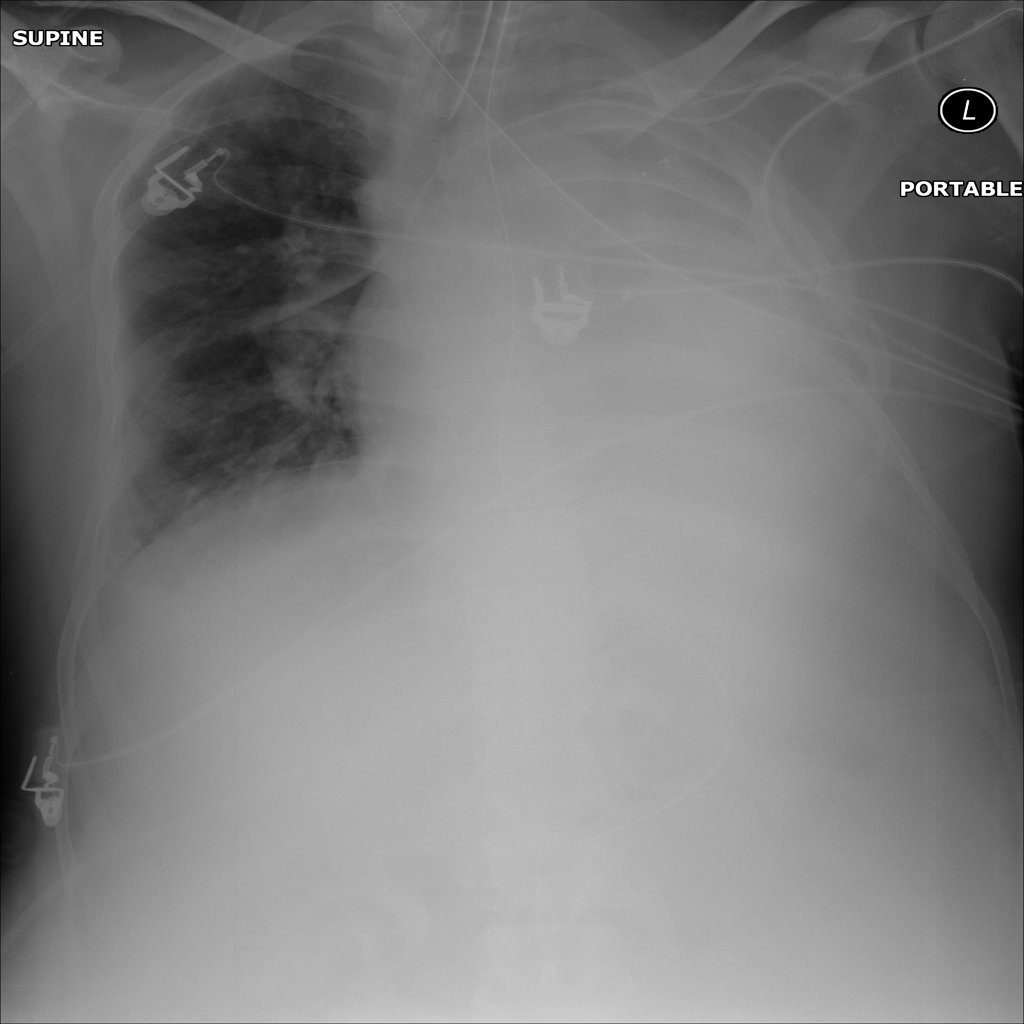

AP

PAT-B9C3 · IMG-000Atelectasis

PAT-B9C3 · IMG-000